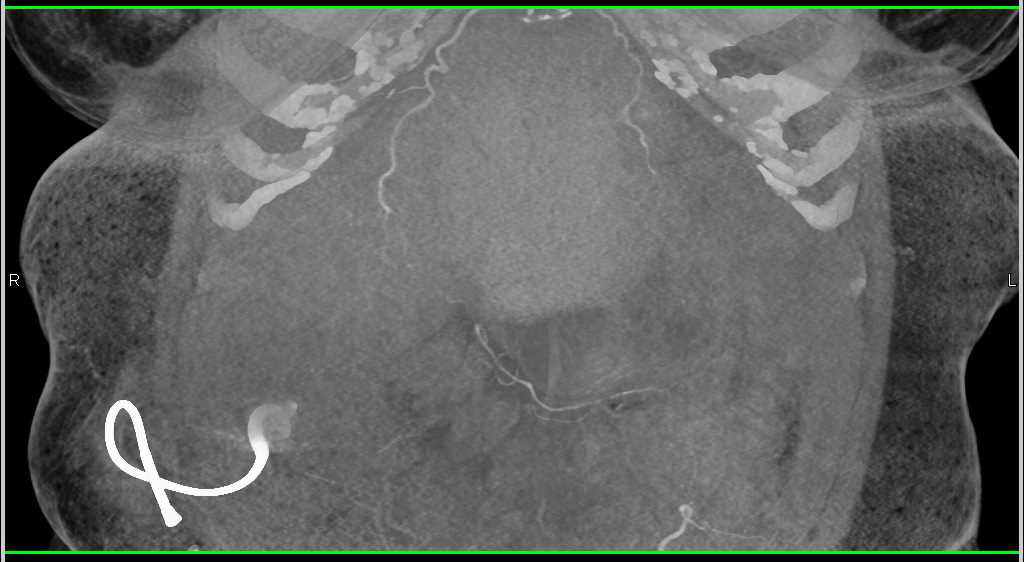

Failed Renal Transplant with Right Lower Quadrant Bleed